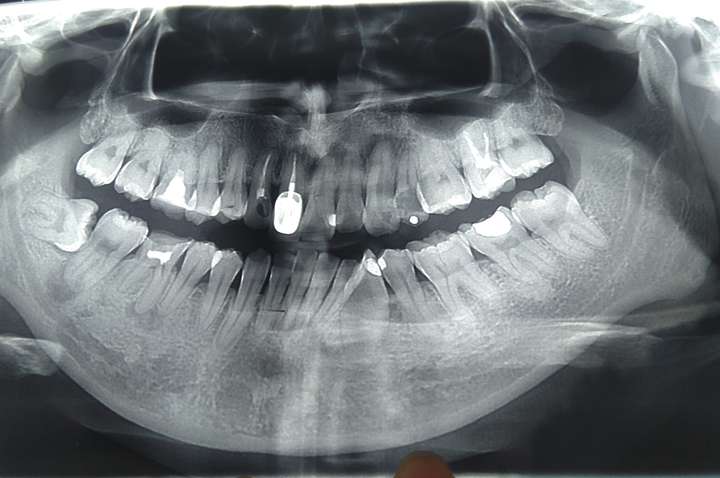

牙齿ct图片

牙齿ct图片 #拔牙后的我 - 抖音

牙齿ct怎么看全景